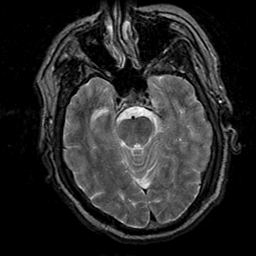

Subacute Stroke, overlay -- Slice #8

[Home][Help][Clinical] Slice 8